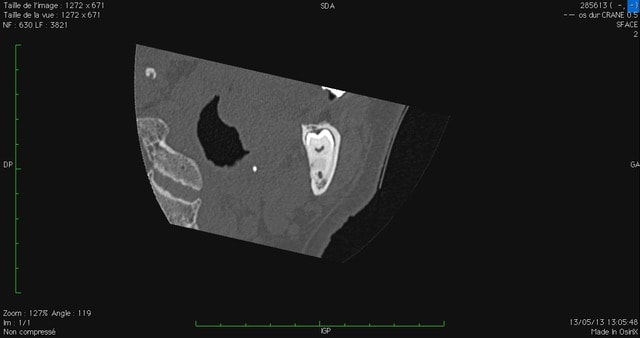

Patient d'environ 45-50, consultation fortuite, voilà ce que je trouve.

D'un côté, la situation est juste un peu tendue : la dent repose franchement sur le NDI.

De l'autre, les deux racines le pince littéralement.

Tiens, voilà du boudin ;) :

- CT 1 et 2 : le côté gauche, LE gros morceau

- CT 3 et 4 : le côté droit, dont on peut tout de même se demander si le nerf ne sera pas un peu adhérent à l'apex.